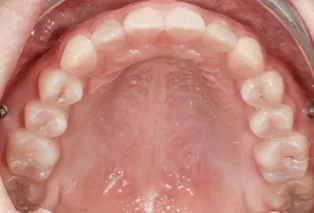

Intraoral photos after treatment